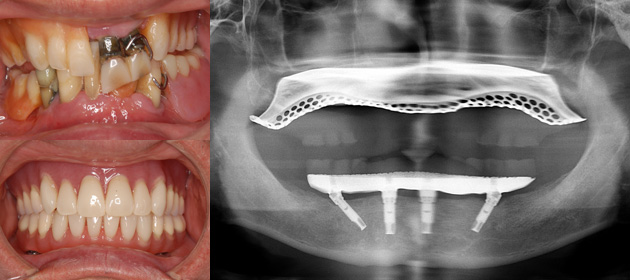

All-on-4 (6)の治療例

下の入れ歯の舌感が悪い